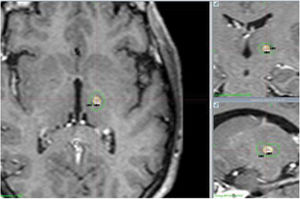

Regarding the findings of the follow-up MRI studies performed at 12 months, lesions were oval-shaped and their centres coincided with the target location in all follow-up studies. The mean volume of T1-hypointense and T2-hyperintense tissue with contrast enhancement was 104 mm3, with a median of 91.5 mm3 (Fig. 4).